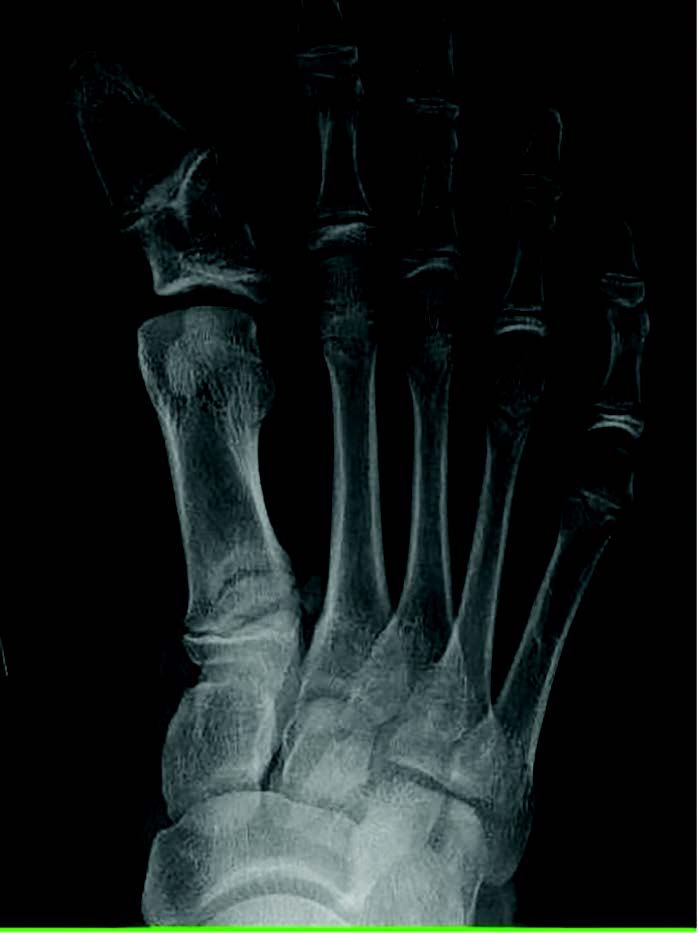

Secondary hallux varus typically relates to great toe polydactyly, a delta phalanx, longitudinal epiphyseal bracket syndrome, and metatarsus adductus (see images above).6 Historically, there is also mention of a tertiary type, associated with severe skeletal abnormalities such as diastrophic dwarfism.7 Unfortunately, the literature is sparse regarding pediatric hallux varus, but within my pediatric population we see kids developing hallux varus who do not have a history of metadductus or even a spastic abductor (see images below).

Within our database, to date, we have not seen a negative intermetatarsal angle in any idiopathic hallux varus case. We routinely see normal intermetatarsal angles and often see some greater than 10 degrees. We routinely see normal sesamoid positions. In our experience, the deformity is almost always a negative PASA deformity. For iatrogenic, it seems like everyone focuses on the sesamoids, but there can be multiple permutations of sesamoid shape, position, or even lack of sesamoids. I then wondered if metatarsal length played a role, but my archives show multiple cases with short and long first metatarsals (see images below). All have the same etiology, incongruent first MTPJ, and negative PASA.